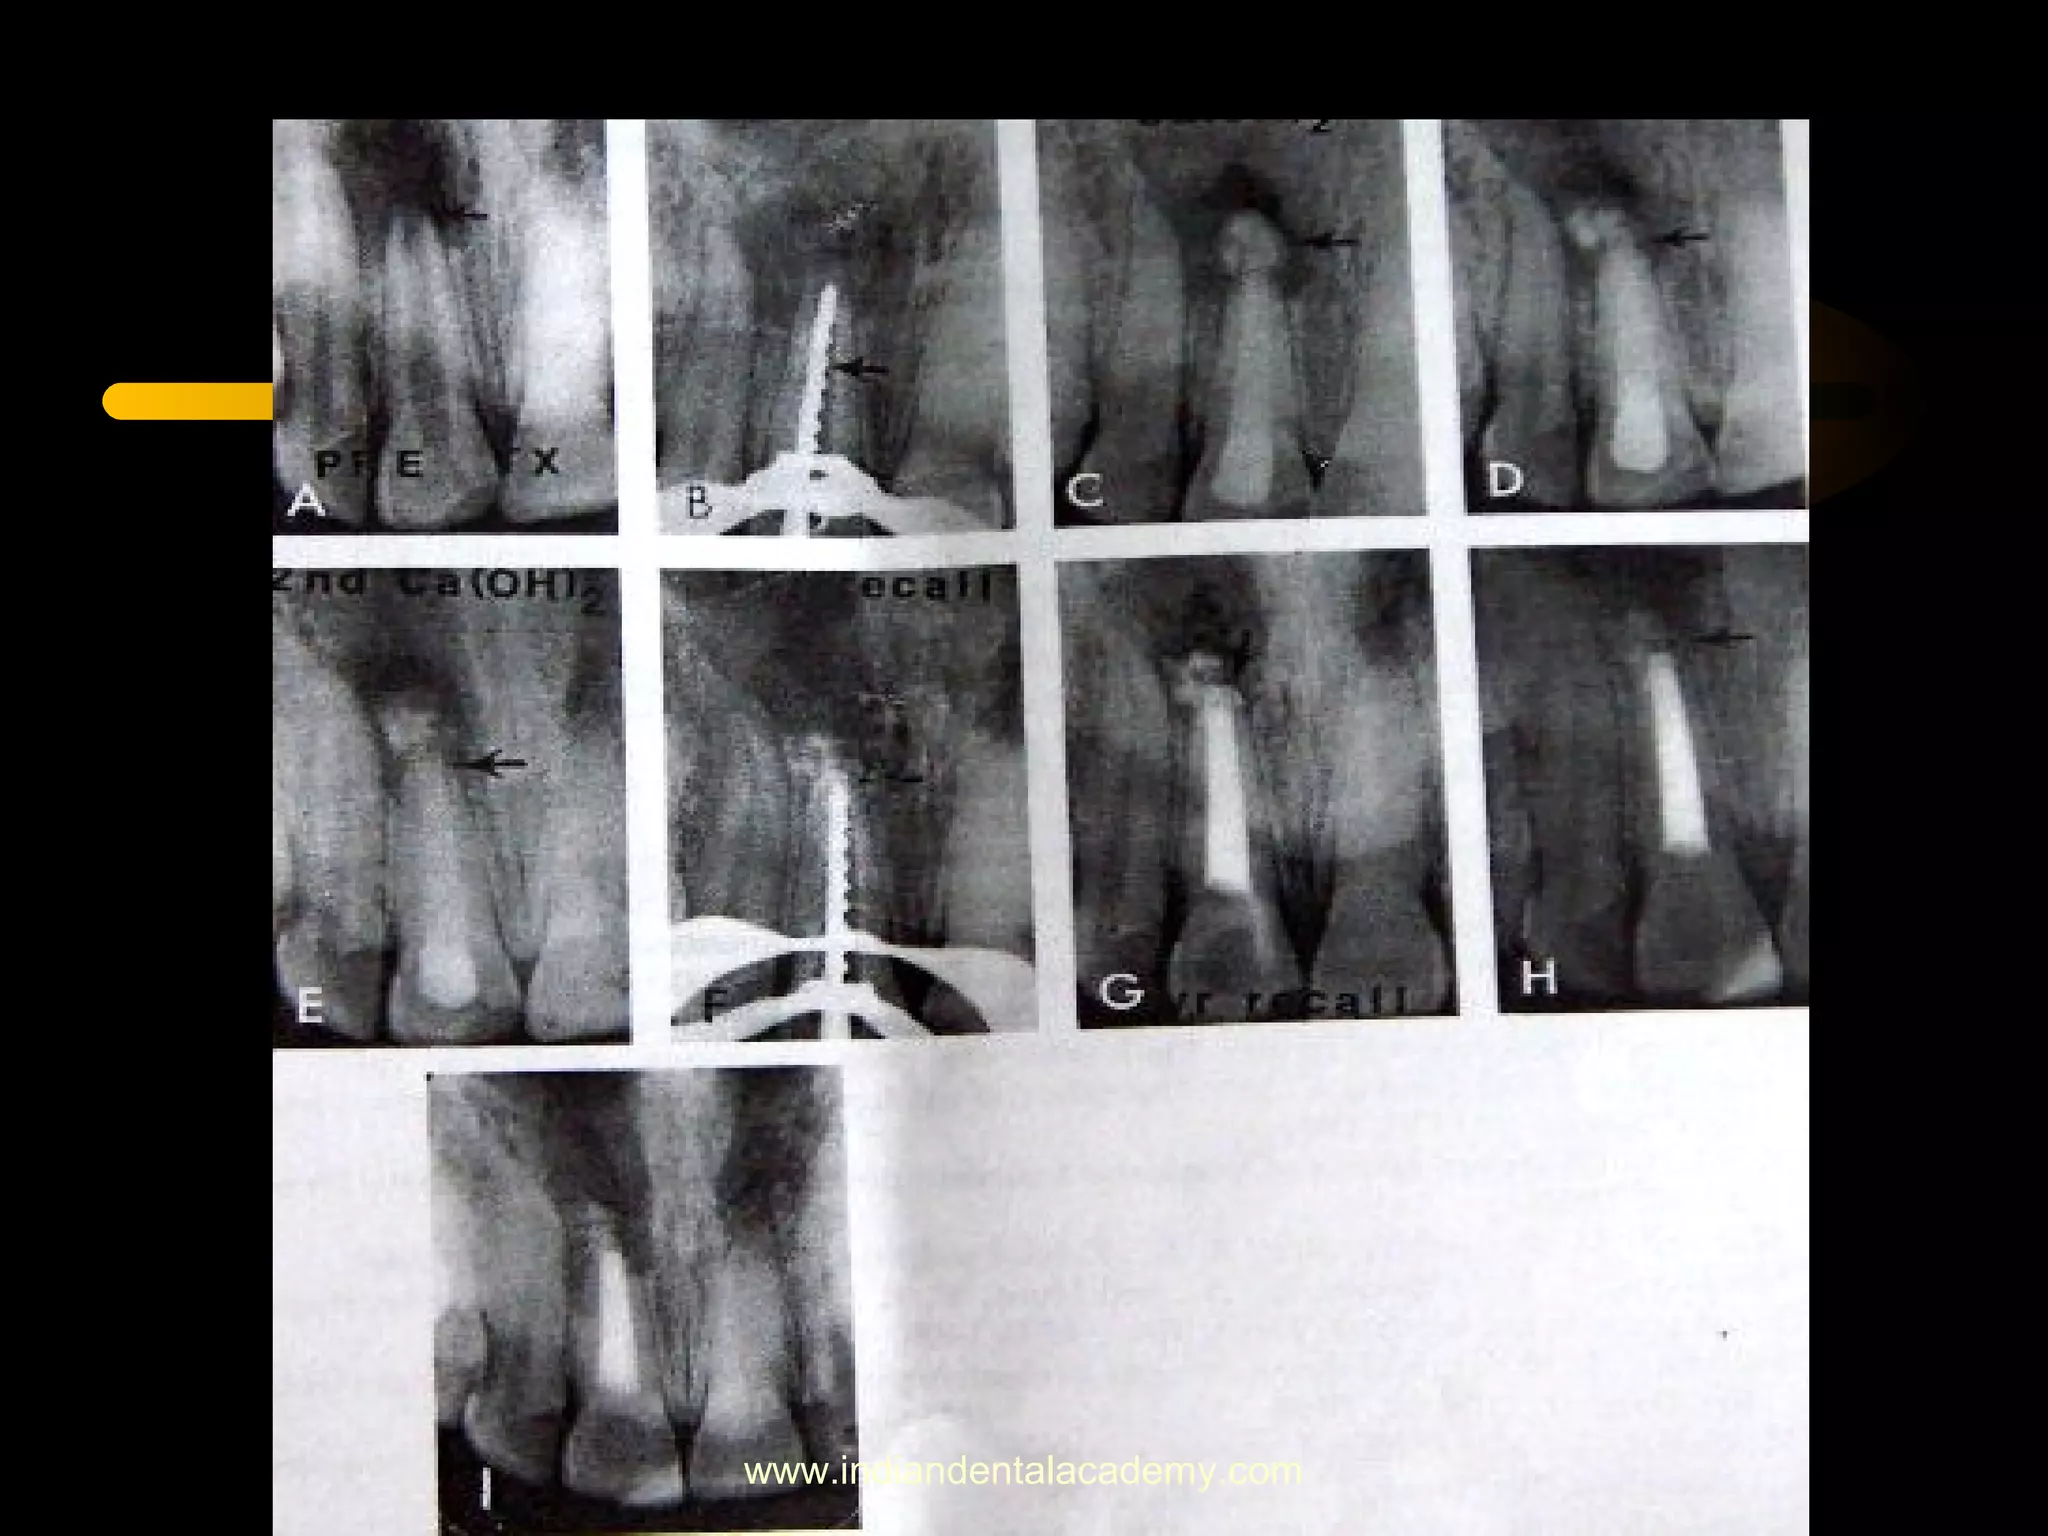

• Time required for apical barrier formation:

Sheey and Roberts : 5- 20 mnths

Finucane and Kinirons: 34.2 weeks ( range :13-67 weeks)

Cvek : presence of infection delays the closure

Kleier and barr : 5 – 15.9 mnths delay in the prescence of